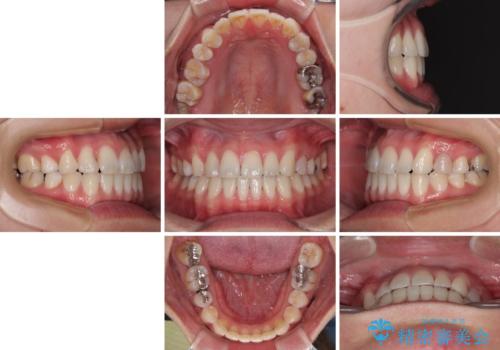

上下前歯のデコボコを気にして来院された患者様です。

ワイヤー矯正でもマウスピース矯正でも可能でしたが、短期間で、自身の手を煩わせることなく治療を行いたいとのことで、ワイヤー装置にて矯正治療を行うこととしました。

舌の突出癖により、治療過程でスペースが多くできましたが、舌のトレーニングを頑張っていただき、1年強で終えることができました。